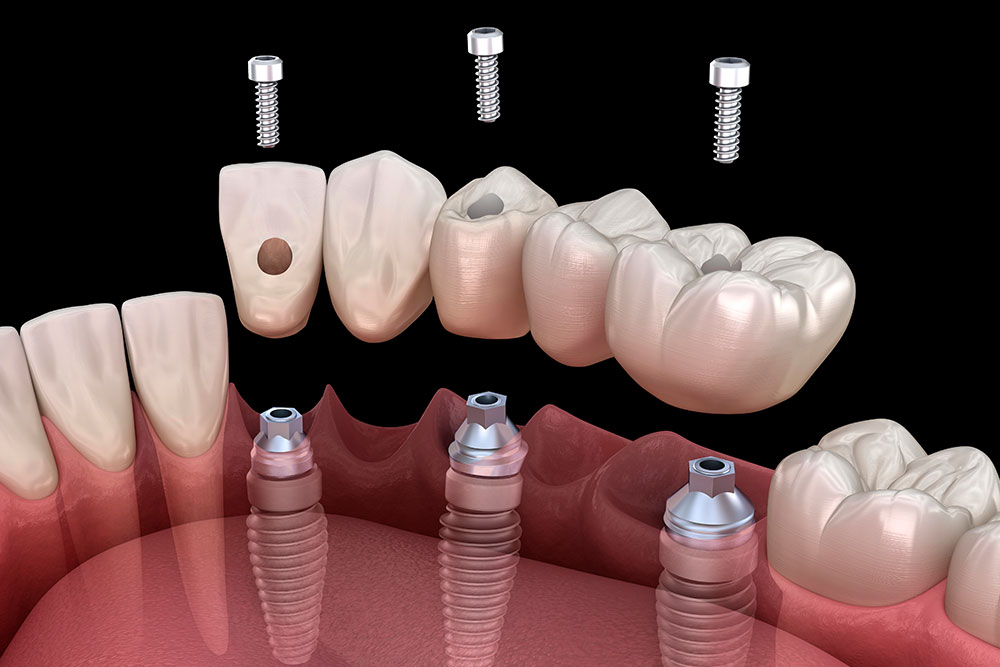

5 Common Mistakes To Avoid When Placing Dental Implants

Dental implants offer patients permanent solutions for missing teeth, but correctly placing them takes skill, …

6 Dental Implant Tools Every Dentist Should Have

Dental implant procedures require precision, expertise, and the right set of tools. Using high-quality dental …